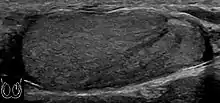

Doppler ultrasound of epididymitis, seen as a substantial increase in blood flow in the left epididymis (top image), while it is normal in the right (bottom image). The thickness of the epididymis (between yellow crosses) is only slightly increased (7 mm).

Doppler ultrasound of the scrotum of the same case, in the axial plane, showing orchitis (as part of epididymo-orchitis) as hypoechogenic and slightly heterogenic left testicular tissue (right in image), with an increased blood flow. There is also swelling of peritesticular tissue.